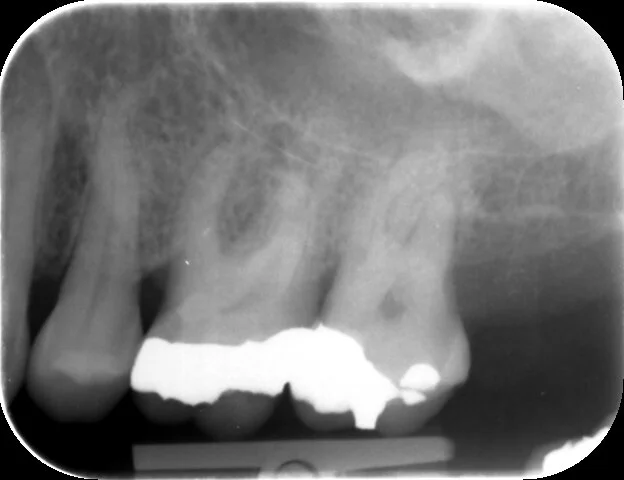

An apical radiolucency on the UL6 is one of the signs of apical periodontitis for this tooth

All four canals have well condensed root fillings with good apical-coronal seals